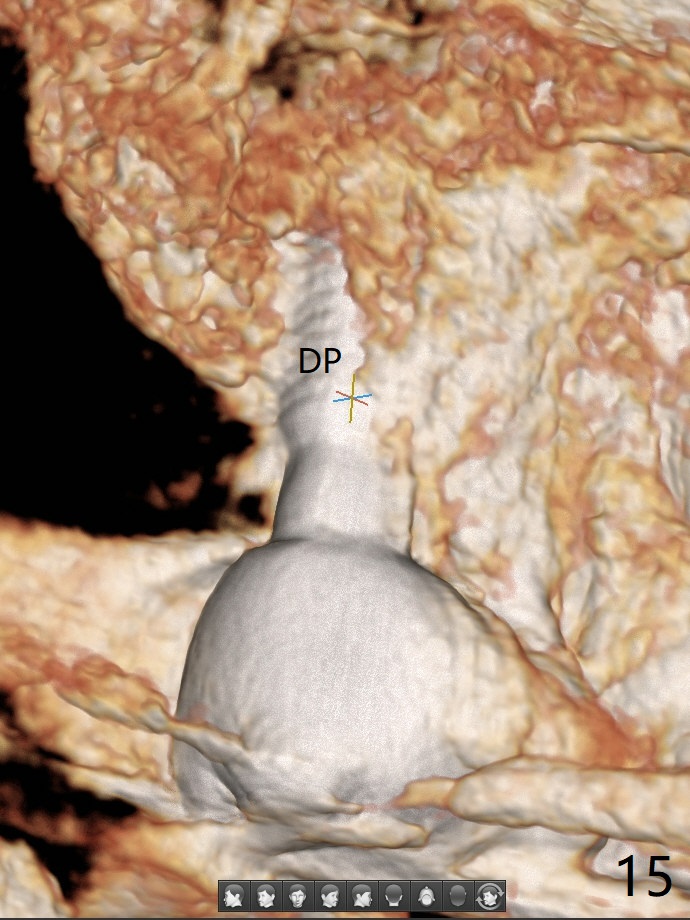

The septum is found to be pointed after extraction of the tooth #14 (Fig.1 *). The septum is flattened with Rongeur (Fig.2 *) prior to osteotomy. Because of interference of the mesial bone (Fig.3 *), osteotomy does not reach the depth with use of stopper. Without the latter, a 5x11.5 mm implant barely penetrates the sinus floor (Fig.4 (no postop nasal hemorrhage)). Also due to the mesial bone interference, a 6.5 mm abutment is not seated. Finally a 5.5x7(5) mm abutment is placed for an immediate provisional. Periodontal dressing is applied to cover the buccal repaired gingiva (Fig.5 *). There is minimal thread exposure after removal of the provisional nearly 2 months postop (Fig.6). The provisional does not return for easy self cleansing. In fact this is not an easy task, because of the posterior position (Fig.8 (after Piezo scaling)). The distal implant remains exposed; the abutment is removed and a healing screw is placed (Fig.9). The implant should have been subcrestal distally (Fig.7 <, nearly 3 months postop). One month later, the implant seems to be buried (Fig.10). The straight abutment is changed to an angled one (4.5 x15 degree A (5) mm) before impression retake (Fig.11,12 (<, dashed line: access hole)). The implant should have been placed more mesial (Fig.13). Surgical guide is needed. There is no implant exposure clinically or in CBCT sections 1 year 2 months post cementaton (Fig.14), although 3 D image suggests missing distopalatal plate (Fig.15).